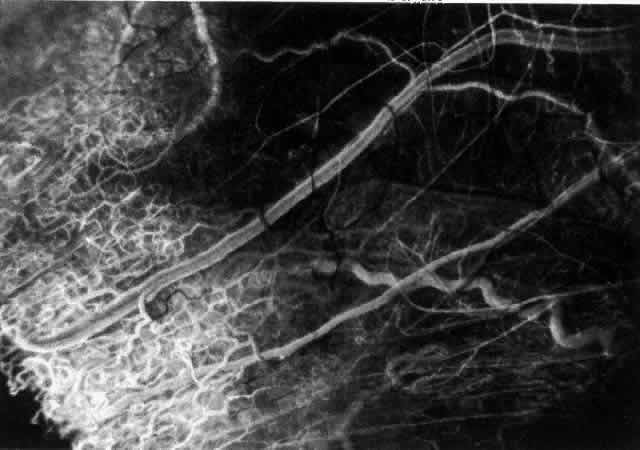

With the increasing use of anterior segment fluorescein angiography in the early detection of severe necrotizing disease of the sclera, it is necessary to have an understanding of the normal anatomy of the vasculature of the anterior segment of the eye.3–5 The blood supply to this region is enormous, being derived from the anterior ciliary arteries, but with extensive collateral arterial anastomoses to the posterior ciliary arteries at the root of the iris (Fig. 1). The anterior system is readily visible with the slit lamp and by anterior segment fluorescein angiography, especially if the eye is inflamed, and its recognition is of vital importance in the differentiation of episcleral and scleral conditions. The separation and displacement of these vascular layers give the most important clinical clues to the site and, hence, the severity of the inflammation. On slit lamp examination, three layers of vessels are readily visible. The conjunctival plexus, which is the most superficial layer of vessels, can be moved over the underlying structures. The superficial episcleral capillary plexus (Fig. 2) is a radially arranged series of vessels lying within the parietal layer of Tenon's capsule. The vessels in this layer anastomose at the limbus with the conjunctival vessels, with other members of the same plexus, and with the deep plexus. The deep episcleral capillary network (see Fig. 2) is closely applied to the sclera in the visceral layer of Tenon's capsule. The vessels anastomose freely with each other, forming a syncytium. The large vessels to and from the intrascleral plexus traverse the episclera near the insertions of the muscles. The conjunctival and superficial episcleral vessels can be blanched with 1:1000 epinephrine or 10% phenylephrine, but the deep vessels are affected slightly. This is of considerable assistance when attempting to differentiate deep and superficial inflammation.

Fig. 2. The normal relationships of the capillary networks that can be seen with the slit lamp are a conjunctival (easily mobile) network, a superficial episcleral network in the parietal layer of Tenon's capsule, and a deep episcleral plexus closely applied to the sclera. These relationships are much more obvious in inflamed eyes (see Figs. 13, 14, and 30). (Watson PG, Hayreh S, Awdry P: Episcleritis and scleritis. Br J Ophthalmol 52(3):278– 279, 1968)

Episcleral Circulation

Immediately after their origin by bifurcation of the anterior ciliary arteries, the contributions to the anterior episcleral circle divide again to give recurrent branches that run posteriorly and subdivide to form a netlike episcleral plexus (see Fig. 5; Fig.7). The variability of the positioning of the anterior ciliary arteries inevitably leaves large areas of episclera far from such an arterial supply (see Figs. 4, 6, and 7). These areas receive other posterior branches from the episcleral circle. Where the circle runs deep within the sclera, such branches appear as isolated perforating vessels (see Fig. 6). They fill very shortly after the episcleral circle, and they also divide repeatedly as they run posteriorly.